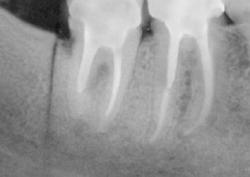

Зуб удаляют не только при сильной боли. Иногда пациент почти не предъявляет жалоб, но на рентгеновском снимке видно воспаление у корня, трещину, разрушение ниже десны или риск осложнений для соседних зубов. В таких ситуациях врач предлагает удаление как безопасный выход и заранее объясняет, какие варианты восстановления подойдут после заживления.

Метод выбирают по рентгеновскому снимку и осмотру. Врач учитывает форму корней, объем разрушения, состояние кости и мягких тканей. В практике применяются:

Без диагностики качественно удалить зуб сложно. В КДС перед вмешательством врач проводит осмотр, оценивает состояние десны, соседних зубов и прикуса. Далее выполняют рентгеновский снимок, чтобы увидеть корни, форму каналов, состояние кости и возможные воспалительные изменения.

Диагностика помогает выбрать тактику и снизить риск осложнений. Врач заранее понимает, потребуется ли разделение корней, наложение швов, дополнительная обработка лунки, а также прогнозирует сроки заживления.